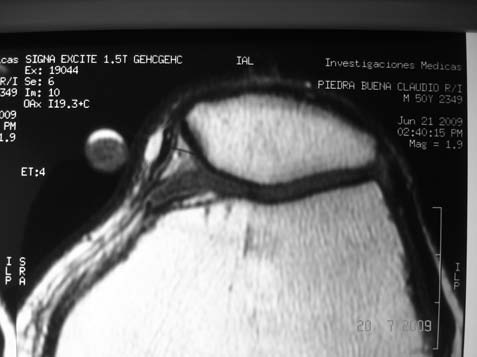

RX simple: buen eje patelofemoral, no se halló evidencia de cuerpo libre osteocondral. (Fig. 1)Resonancia magnética: se identificó una tumoración en el alerón patelar medial, circunscripta, de 7mm de diámetro, localizada en el sector parapatelar medial, a nivel del plano de sección transversal mediopatelar.T1-T2 sin y con gadolinio. (Fig. 2 A-B)

Figura 2B: Imagen axial en T1 con gadolinio: Se identifica franco realce homogéneo de la imagen, de bordes netos, ovalada, que contacta al ligamento alar interno